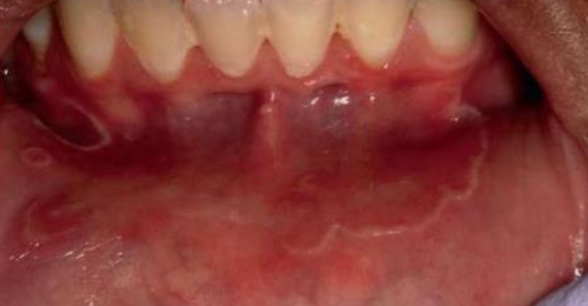

Paraneoplastic Pemphigus (PP)

腫瘤誘導性天疱瘡

• Lymphoma, Chronic lymphocytic leukemia, Castleman disease 患者

• 異常 IL6 → TFH → IL-21 → Plasma cell

• Ab 打 Plakin family Desmoglein 1, 3

• 天疱瘡症狀

• 突發、多發水泡

• 高致死

• 會出現在手掌腳掌

• 嘴唇出血性結痂

• 紅斑(erythema), 瀰漫性不規則潰瘍(diffuse, irregular ulceration)

• 阻塞性細支氣管炎(bronchiolitis o bliterans)

alt text alt text alt text

• Dermis 慢性發炎浸潤

• 上皮內、下都裂